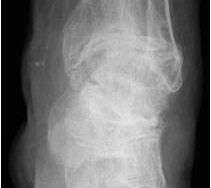

• Primäre oder posttraumatische Arthrose des OSG und USG (Abbildung 1, Abbildung 2).